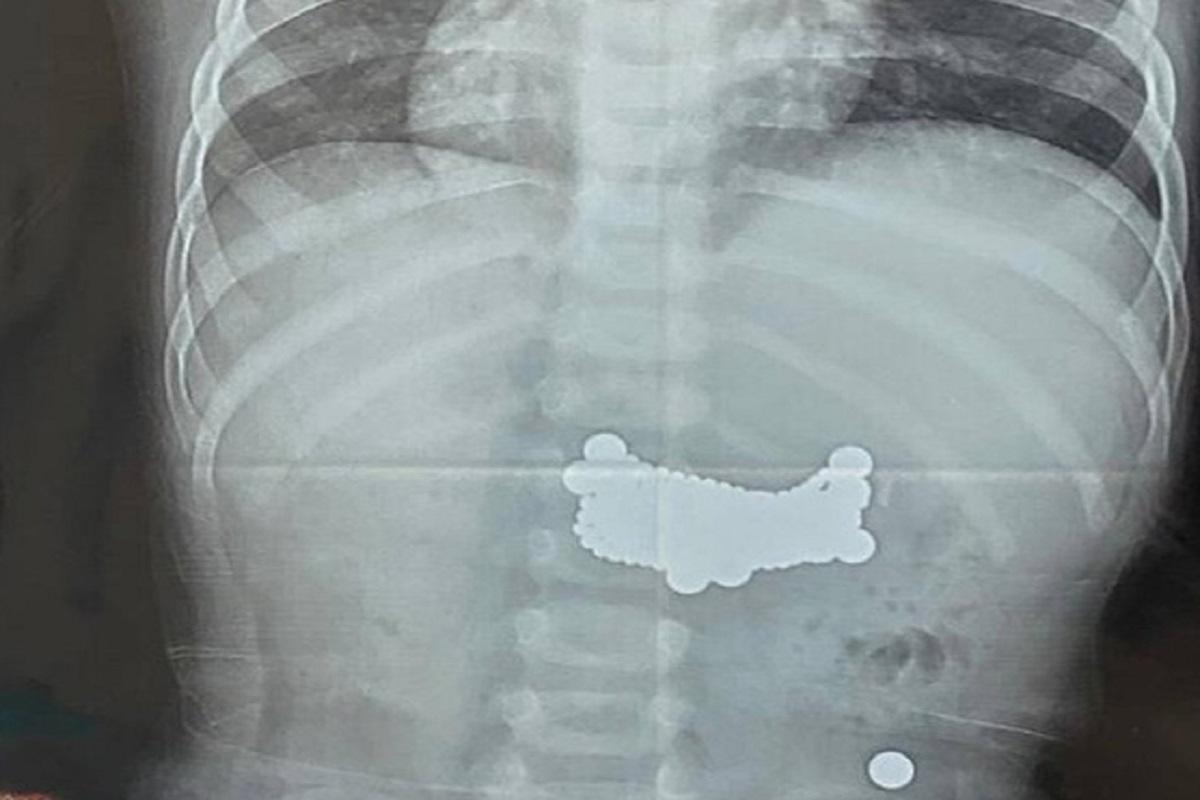

Во время томографического исследования врачи обнаружили множественные инородные тела, распределенные по всему желудочно-кишечному тракту. Как выяснилось в ходе дальнейшего осмотра, ребенок ранее проглотил 11 небольших магнитов. По данным медиков, эпизод произошел задолго до госпитализации, однако мальчик из-за стеснительности и страха не сообщил о случившемся родителям.

Диагностика показала, что семь магнитов скопились в желудке, еще четыре продвинулись в тонкую кишку. За время нахождения в организме магниты успели сцепиться между собой и повредить стенку желудка, что привело к перфорации и потребовало немедленного оперативного вмешательства.